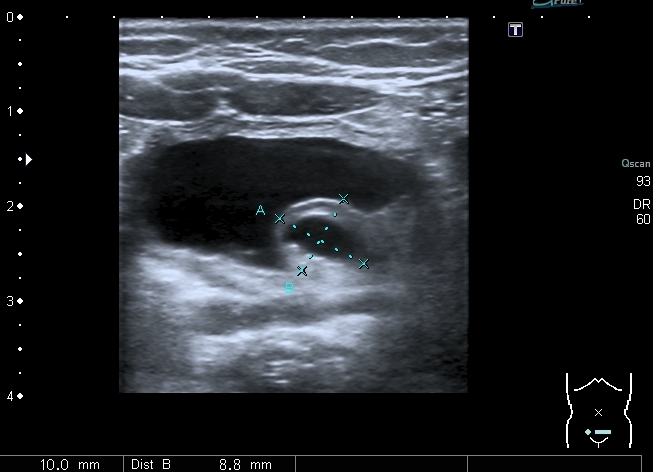

При УЗИ: правая почка - не изменена, в левой - незначительное расширение ЧЛС

В нижней чашечке левой почки - конкремент до 5 мм

Конкремент даёт твитлинг - артефакт